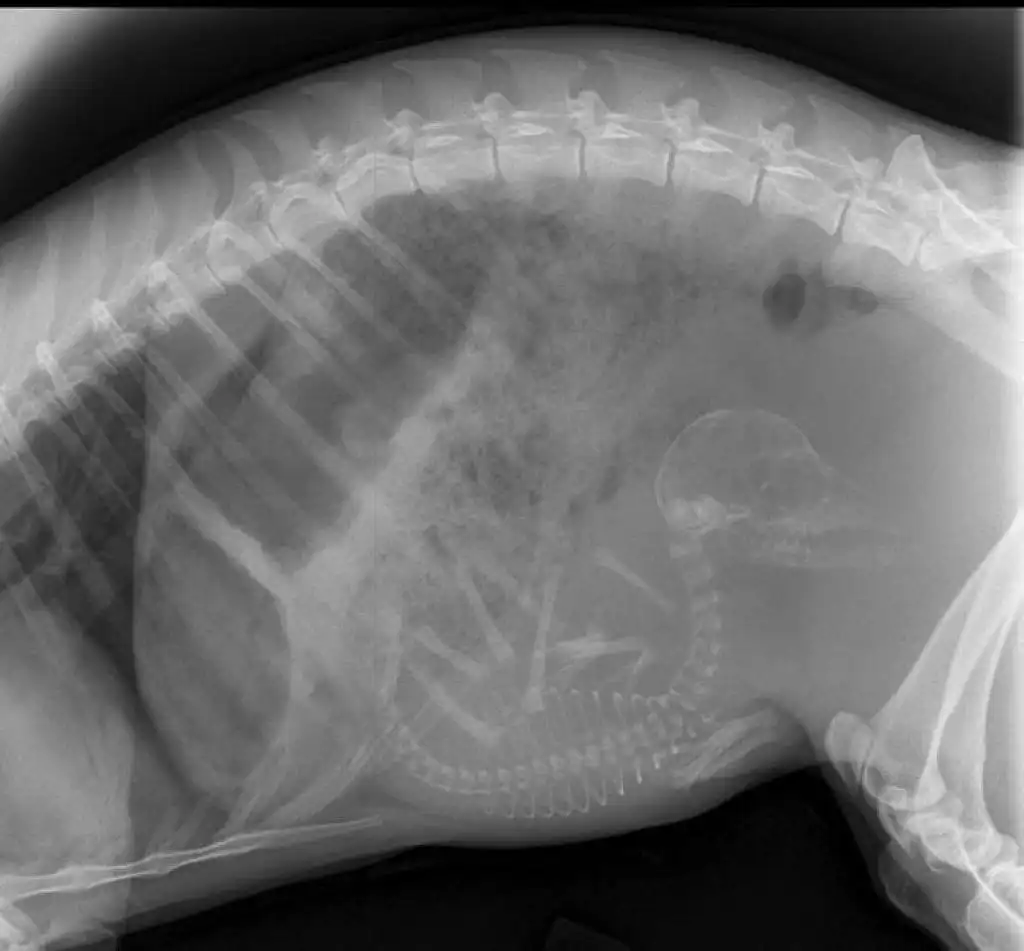

Беременная собака